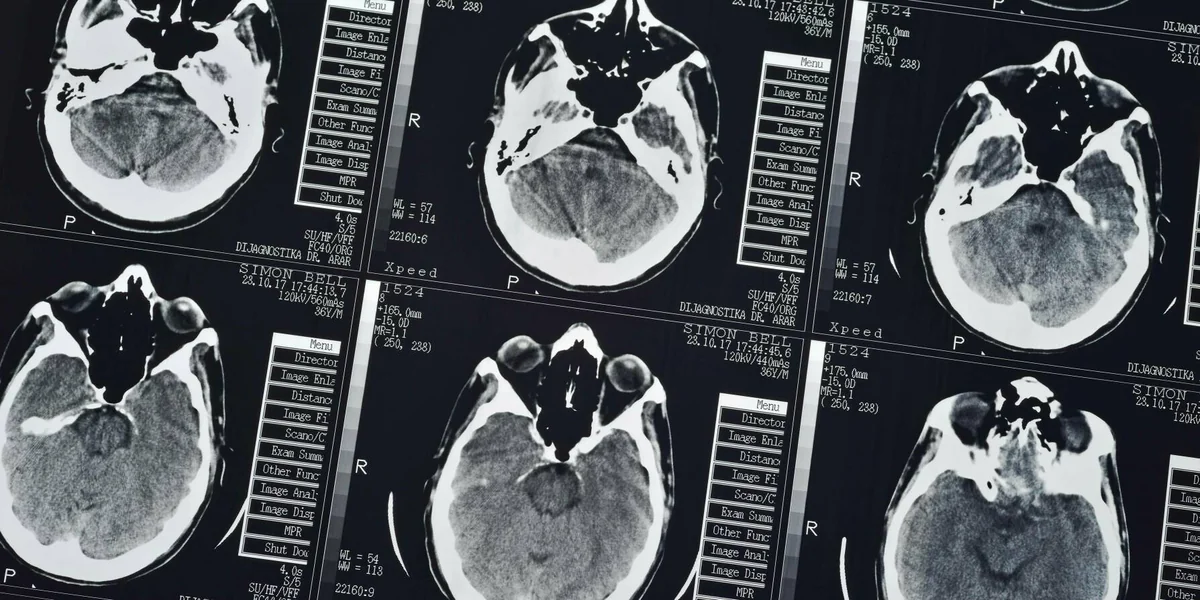

In der medizinischen Diagnostik können Algorithmen dazu beitragen, tomografische Aufnahmen schneller und besser auszuwerten Foto: ImageBroker/imago